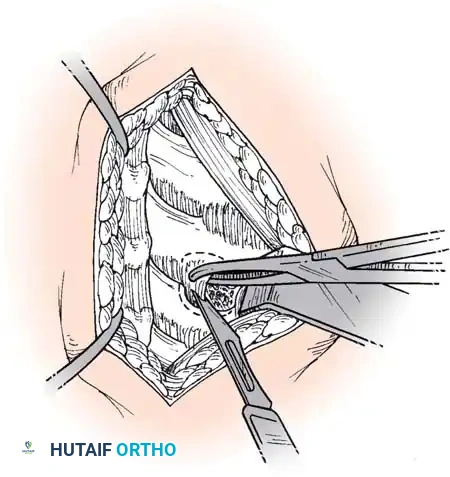

Step 3: Decompression

The posterior longitudinal ligament (PLL) is carefully identified and often resected to ensure no extruded disc fragments remain in the epidural space. High-speed burrs and Kerrison rongeurs are utilized to resect posterior osteophytes and decompress the uncinate processes bilaterally, ensuring the exiting nerve roots are entirely free.

Step 4: Endplate Preparation and Fusion

The cartilaginous endplates are meticulously decorticated using a curette or burr to expose bleeding subchondral bone, which is critical for arthrodesis. Care must be taken not to breach the structural integrity of the endplate to prevent graft subsidence.